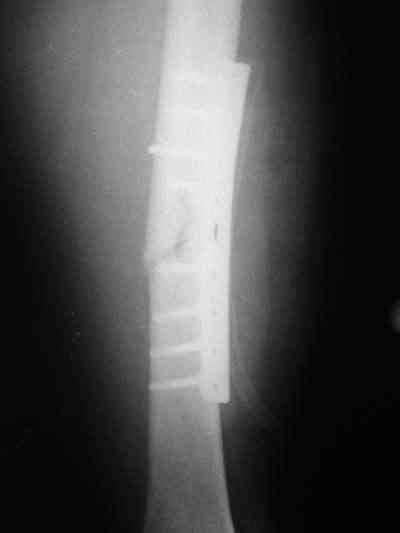

Около 10 дней назад выполнил остеосинтез бедренной кости LC-DCP и DHS по поводу фрагментарного оскольчатого перелома в средней трети и чрезвертельного перелома.

Снимки в приложении.

В приложении и имеющийся в наличии брейс. Приношу извинения за низкое качество снимков.

Качество снимков приемлемое. С нагрузкой категорически не надо спешить - только при уверенных рентгенологических признаках сращения на обоих уровнях в данном случае. Т.е. не только на диафизе, но и в вертельной области. При безупречном синтезе DHS ранняя нагрузка в этой зоне была бы безопасна, все определялось бы сращением диафиза. А поскольку винт в DHS сделали ну о-очень короткий, то ойкнуть не успеете, как

проксимальный отдел бедра в варус кувыркнется.

Глубокоуважаемый Никита!На бедре стоило бы обязательно провести межфрагментарный стягивающий винт и предварительно надо бы слегка изогнуть пластину,ну и может быть трансплантат по внутренней поверхности.А параллельно большому винту DHS провести спонгиозный винт для ротационной стабильности.Так,что с нагрузкой не нада тараписся!

Уважаемый Никита, очень меня расстроило не качество снимков, а сам остеосинтез. Вертельный перелом, пожалуй, еще срастется. А диафиз может преподнести ожидаемое, предуготованное осложнение: несращение и перелом импланта, даже если это суперфмрменная пластина.:(